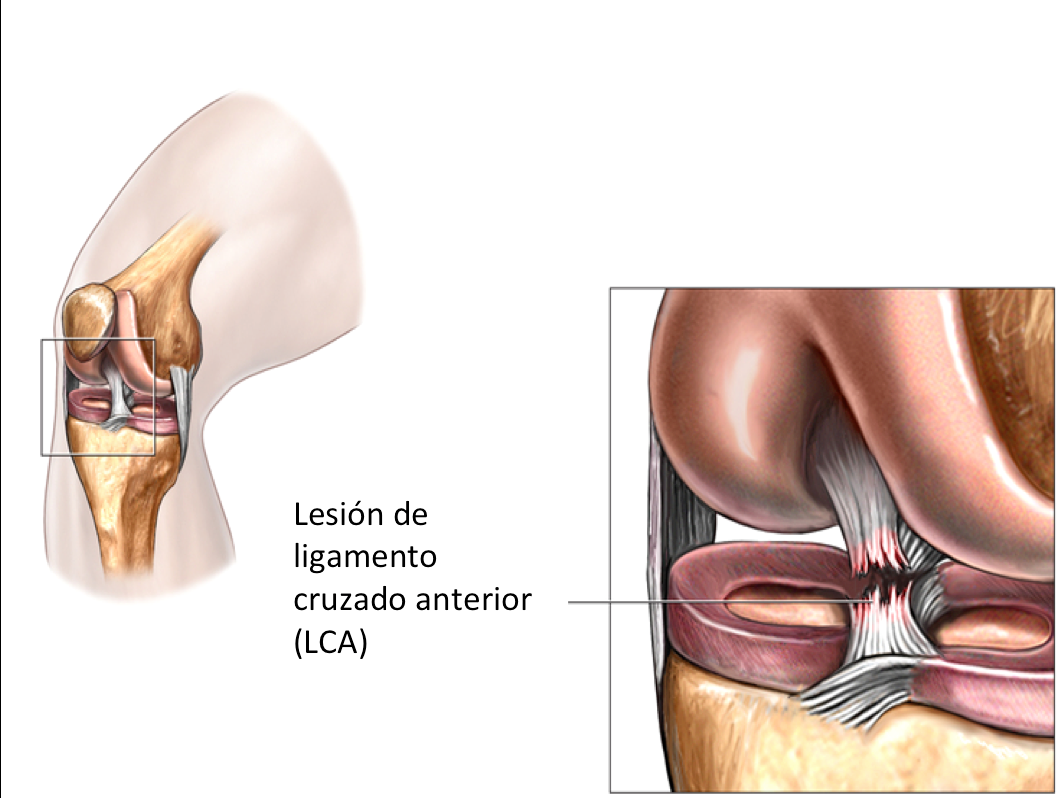

Строение коленного сустава. Повреждения мениска. Разрыв крестообразной связки. Гончаров Е.Н.